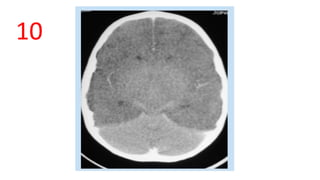

10

White cerebellum sign

• .There is global hypodensity of the supratentorial brain with relative hyperdensity

of the infratentorial compartment.

• obliteration of the surface and central CSF spaces in keeping with the severe

oedema.

• Global Hypoxic-ischaemic injury